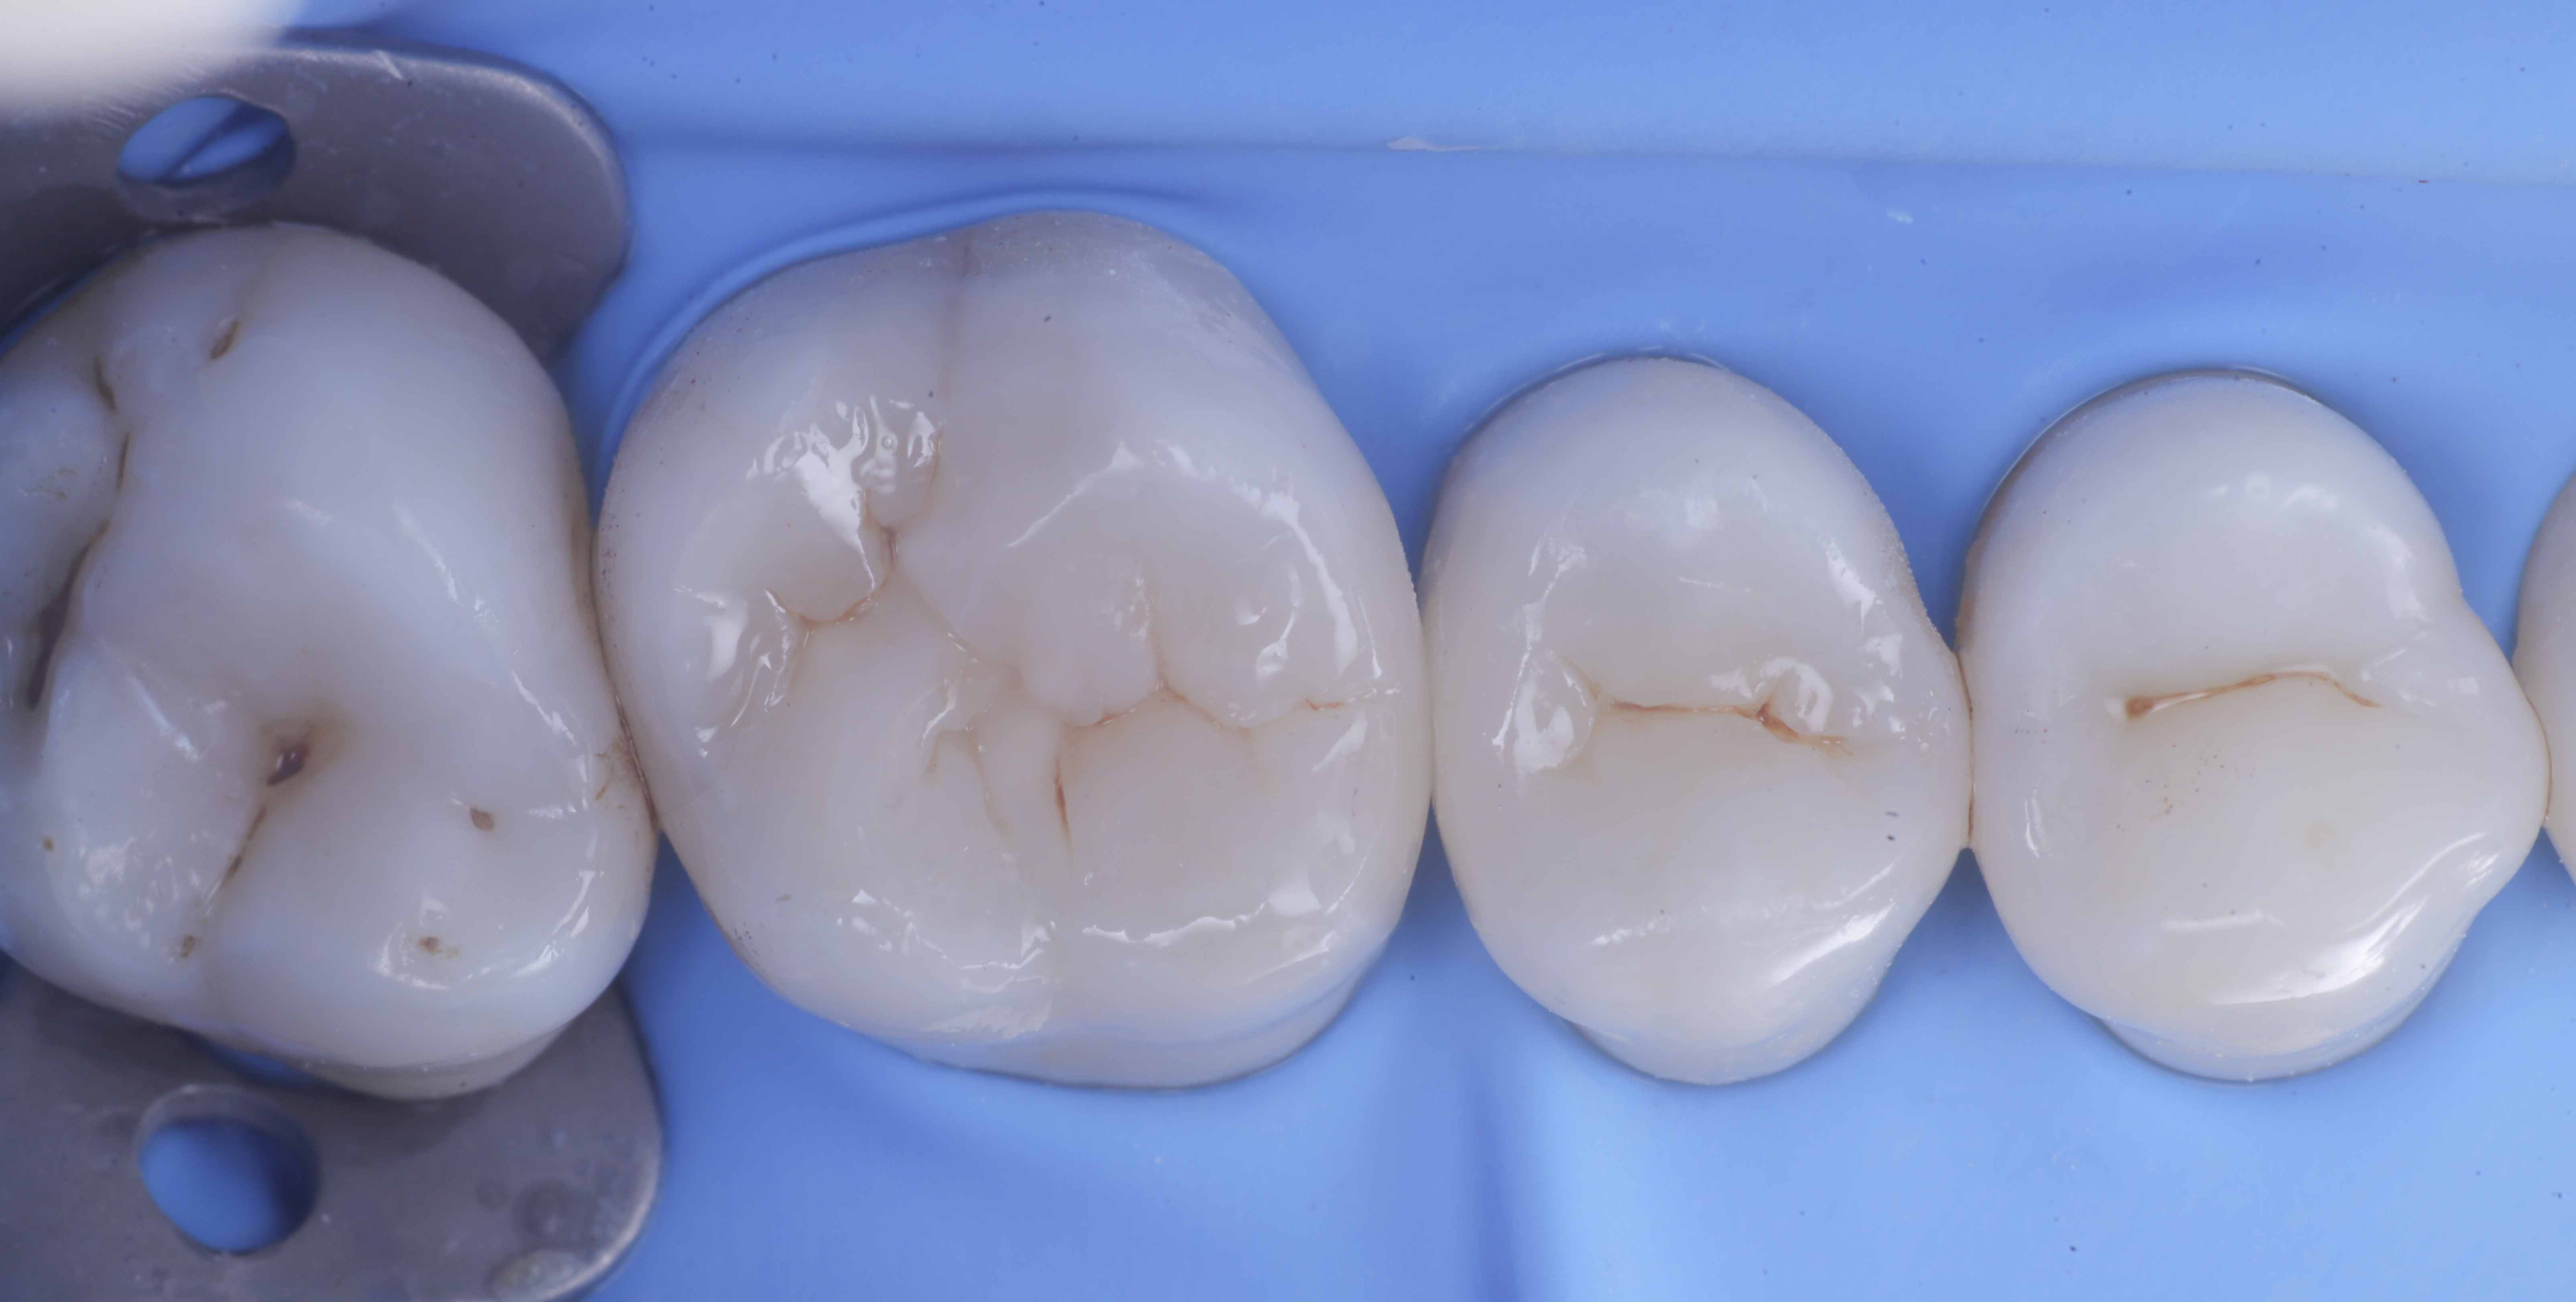

foto 6 Aspetto occlusale delle pareti interprossimali appena create

foto 7 Aspetto vestibolare delle pareti interprossimali appena create